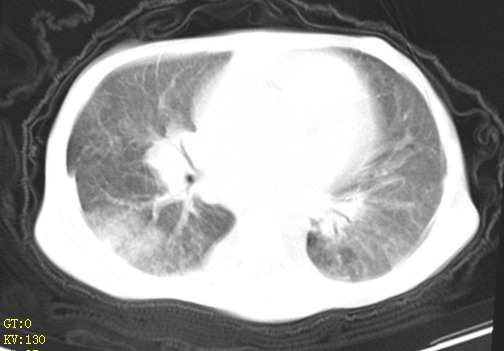

女,12岁,气促、咳嗽2天,3个月前查胸片示:两肺感染,急诊入院查ct,血常规等未检查。

左肺上叶改变考虑继发性肺结核,余双肺重症肺炎不排除h1n1。双侧胸腔少量积液。

双肺中下野不规则片絮状阴影,中外带明显,双侧胸腔少量积液,心影增大,心腔密度减低,隆突下及左侧气管旁见钙化淋巴结影,考虑双肺感染、心衰;建议结合临床除外h1n1并急性心衰,先心不能排除。

两肺多发片絮状模糊影,以下肺外带居多,内见支气管气像,纵膈窗未减影,两侧胸腔积液,心影增大,结合心超,支持重症肺炎,非常时期,甲型h1n1流感不排除。